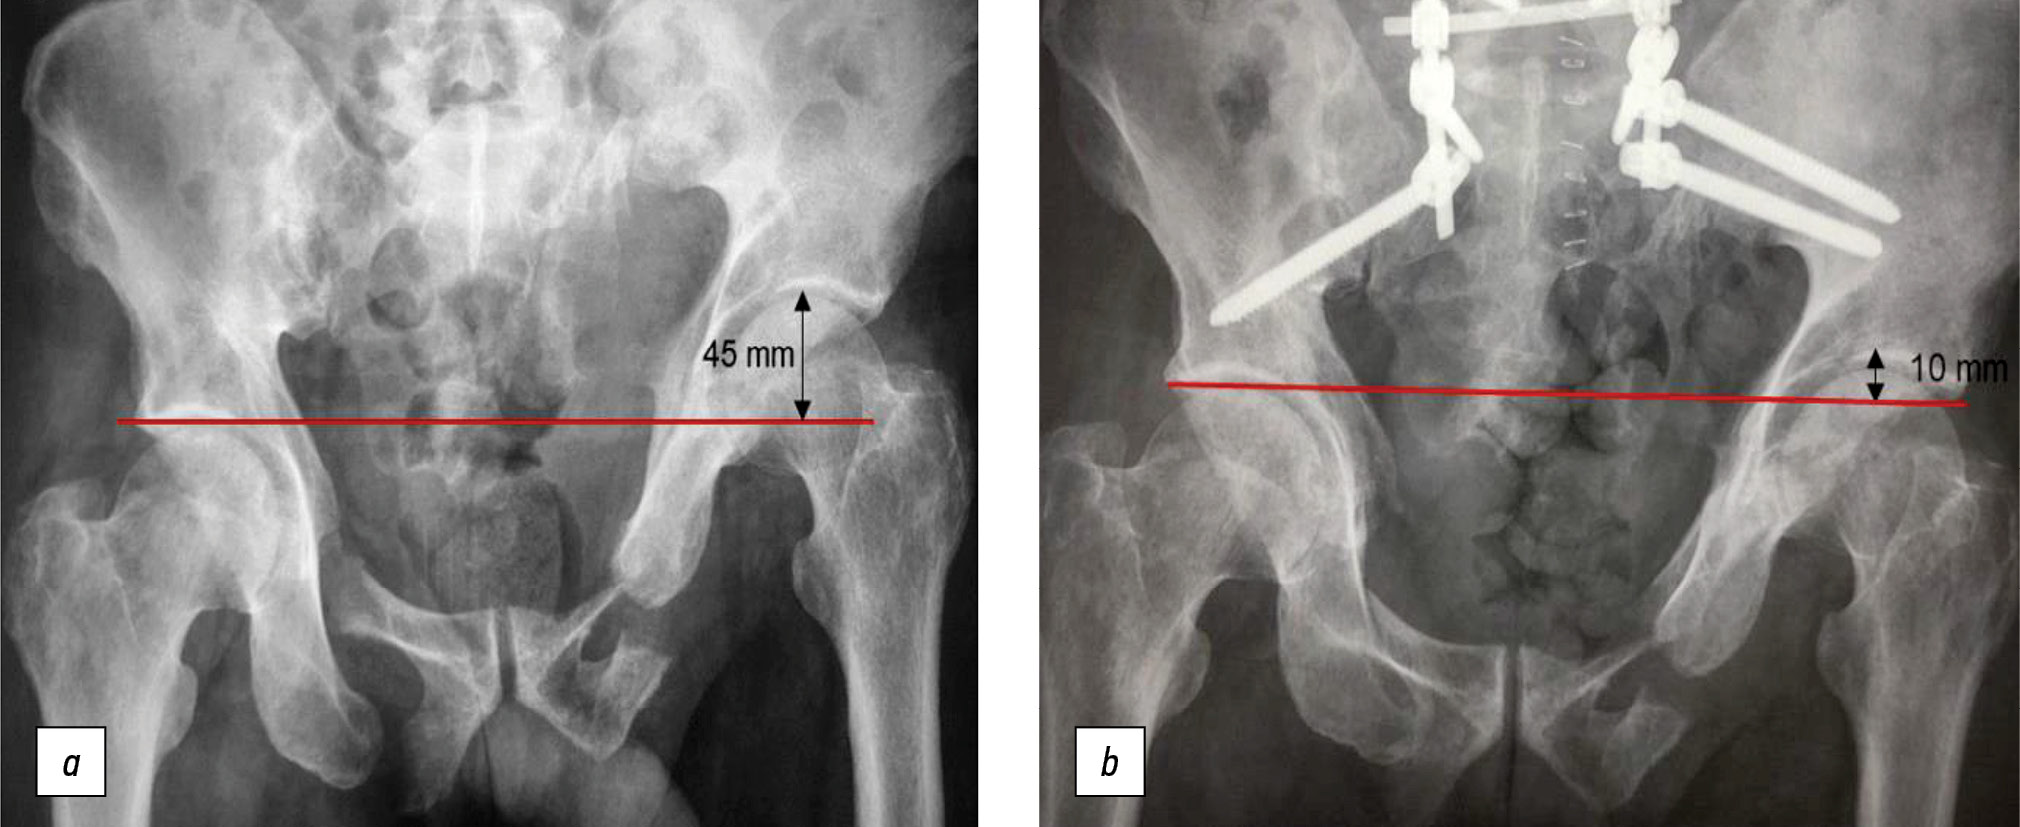

A patient aged 56 years presented 11 months after an injury (fall from the 5th floor). CT showed fractures of the pubis and ischium on both sides, and a longitudinal fracture of the lateral sacral masses on the left side in the Denis 2 area (Fig. 4).

Grade III vertical displacement according to Shlykov classification (45-mm asymmetry of the hip joints) was noted. The patient was on bed rest from the moment of injury, and no verticalization was done. Open repositioning of the left hemipelvis and bilateral PTF were performed. The surgery resulted in a 35-mm displacement and a residual displacement of 10 mm (Fig. 5).

Fig. 5. Overview radiography of the pelvis: а — before surgical treatment; b — after spino-pelvic fixation with open reposition of the left hemipelvis.